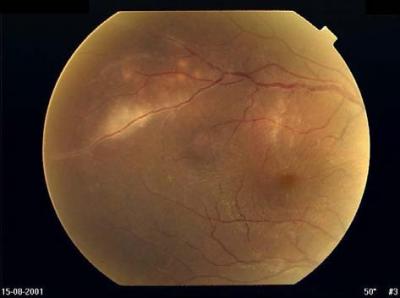

FIGURE 1:	Case 1. Fundus photograph of the right eye showing phlebitis of the superotemporal vein with three adjacent choroidal lesions with macular oedema and disc hyperaemia.